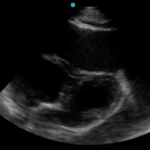

Cardiac tamponade is a rare and life-threatening condition that can be caused by trauma and various medical conditions. Failure to recognize and repair it quickly could lead to significant morbidity or even death. This case demonstrates the electrocardiogram (ECG) findings of low voltage QRS and electrical alternans in cardiac tamponade. It also highlights the classic ultrasound (US) findings of pericardial effusion and right ventricular collapse during diastole in cardiac tamponade. Classic physical exam findings of cardiac tamponade include Beck’s Triad (jugular venous distention, hypotension, and muffled heart sounds) and pulsus paradoxus. This patient only had jugular venous distention and pulsus paradoxus. The case is centered on a 52-year-old male who presented with shortness of breath, wheezing, and a productive cough with streaks of blood. A CT chest was performed which revealed a large pericardial effusion, right upper lobe lung mass, and bilateral pulmonary emboli. A bedside transthoracic echocardiogram was then performed which confirmed the large effusion as well as right ventricular collapse during diastole. Cardiothoracic surgery and interventional cardiology were consulted and both agreed to take the patient to the cardiac catheterization lab for percutaneous drainage of the effusion. Pericardiocentesis was performed and 1.7 liters of serosanguinous fluid was removed and a drain was left in place. He recovered well from the procedure and had an uneventful admission. After reviewing this case, learners should be able to recognize the diagnostic features and various causes of pericardial effusion and cardiac tamponade.